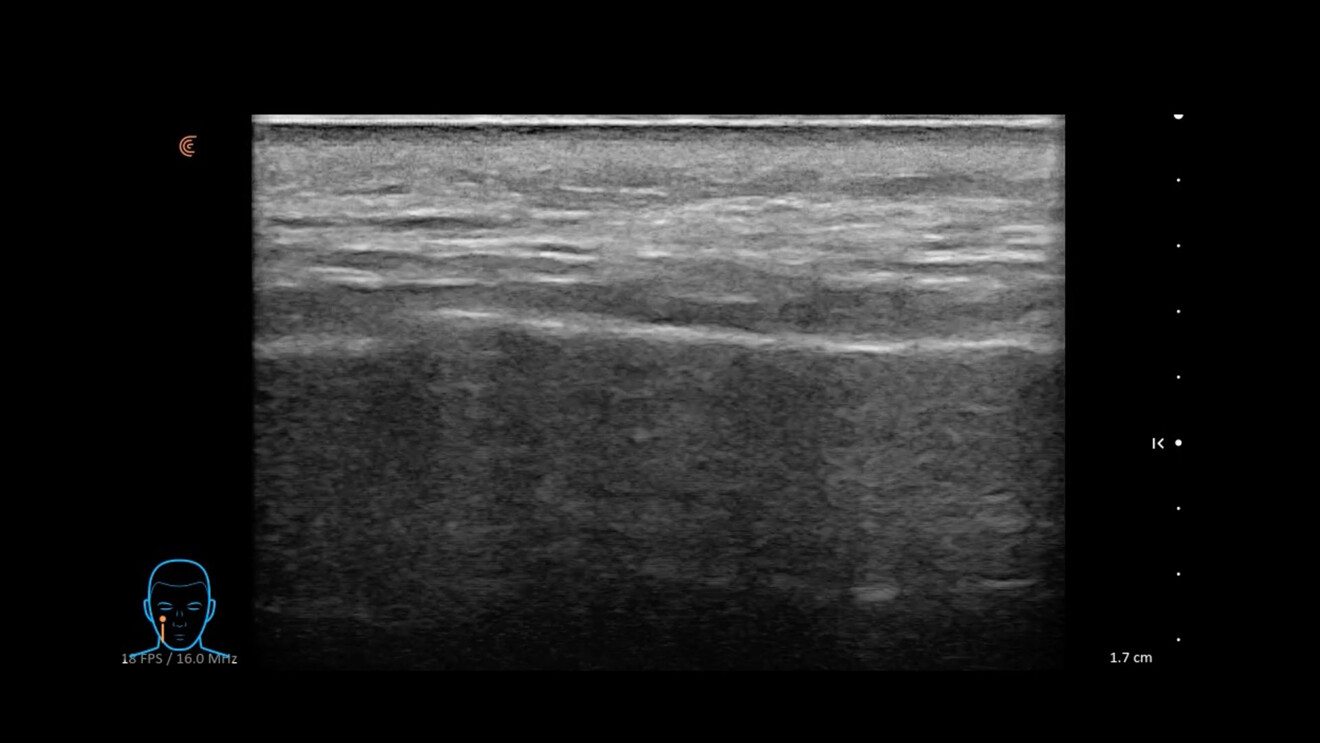

• Mappatura vascolare dinamica: l’integrazione di B Mode, Color Doppler e del Power Doppler rappresentano la frontiera della sicurezza. Vasi critici posti in posizioni anatomiche critiche come l’arteria angolare possono avere decorsi variabili. L’esame ecografico permette di mappare questi vasi prima di inserire l’ago, scegliendo il piano di correzione (superficiale o profondo) che garantisca l’assenza totale di rischio vascolare occlusivo intravascolare o compressivo extravascolare (Fig. 9).

Fig. 9 - L’arteria angolare in Color Doppler.